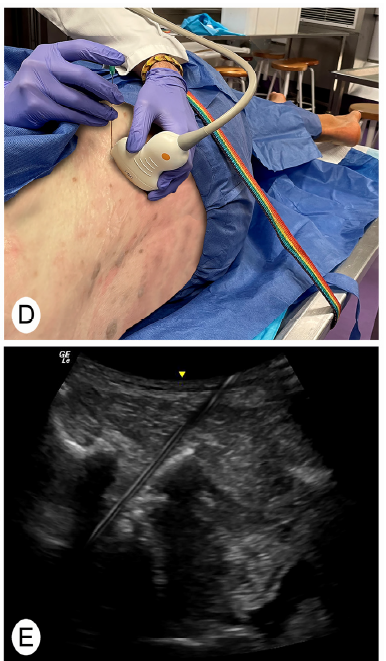

연구진들은

방사선을 사용하는 C-arm 없이,

오직 초음파만으로

허리 디스크가 신경을 누르는 바로 그 지점에

정확히 주사할 수 있는지 확인했습니다.

이 방법은

초음파 가이드 선택적 신경근 차단술(SNRB, selective nerve root block)이라고

부르는데요.

초음파로 우리 몸속을 들여다보며

병의 원인점을 찾아가는 과정입니다.

그리고 초음파로 보면서 신경근 가까이 접근해서

PDRN 연아약침을 주사합니다.

하지만 초음파에서는 도플러 기능을 이용해

혈관을 직접 보면서 시술할 수 있습니다.